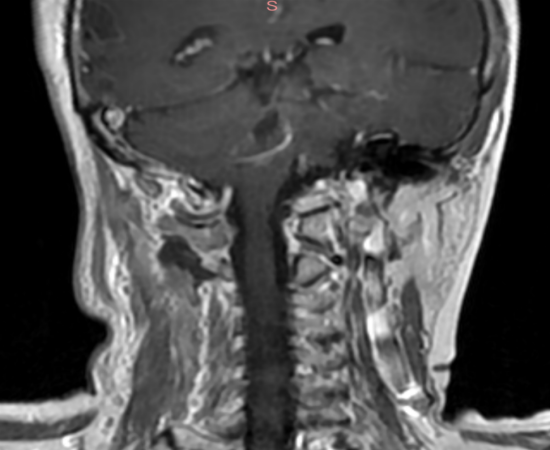

手术中,陈晓丰教授在患者颈部通过一约2.5厘米长切口,精细分离肌肉间隙,建立微创工作通道,在显微镜和神经内镜的双重辅助下,手术团队清晰辨认出肿瘤与椎动脉及脊髓的边界,小心翼翼分离粘连部位,完整移除了哑铃形肿瘤。 患者术后第二天即可下地活动,实现加速康复外科理念。术后影像学检查显示颈椎稳定性完好,肿瘤完整切除,无需额外内固定。

图4:术后72小时复查肿瘤切除完整,无肿瘤残留